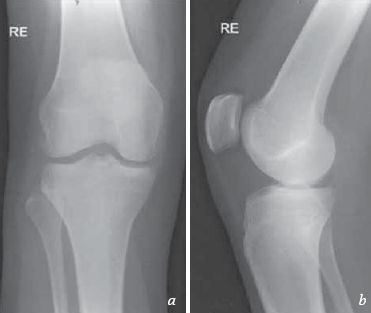

Posteriore kapsel knie. Capsule of right knee-joint distended. Line drawings of posterior capsular area of knee. Symptoms of a Knee Joint Capsule Strain.

An aggressive release near the midline into and past the septum may endanger the popliteal neurovascular bundle. Capsule is incomplete at intercondylar area and contains openings for vascular structures and nerves to enter knee. It is thin in front and at the side and contains the patella ligaments menisci and bursae of the knee.